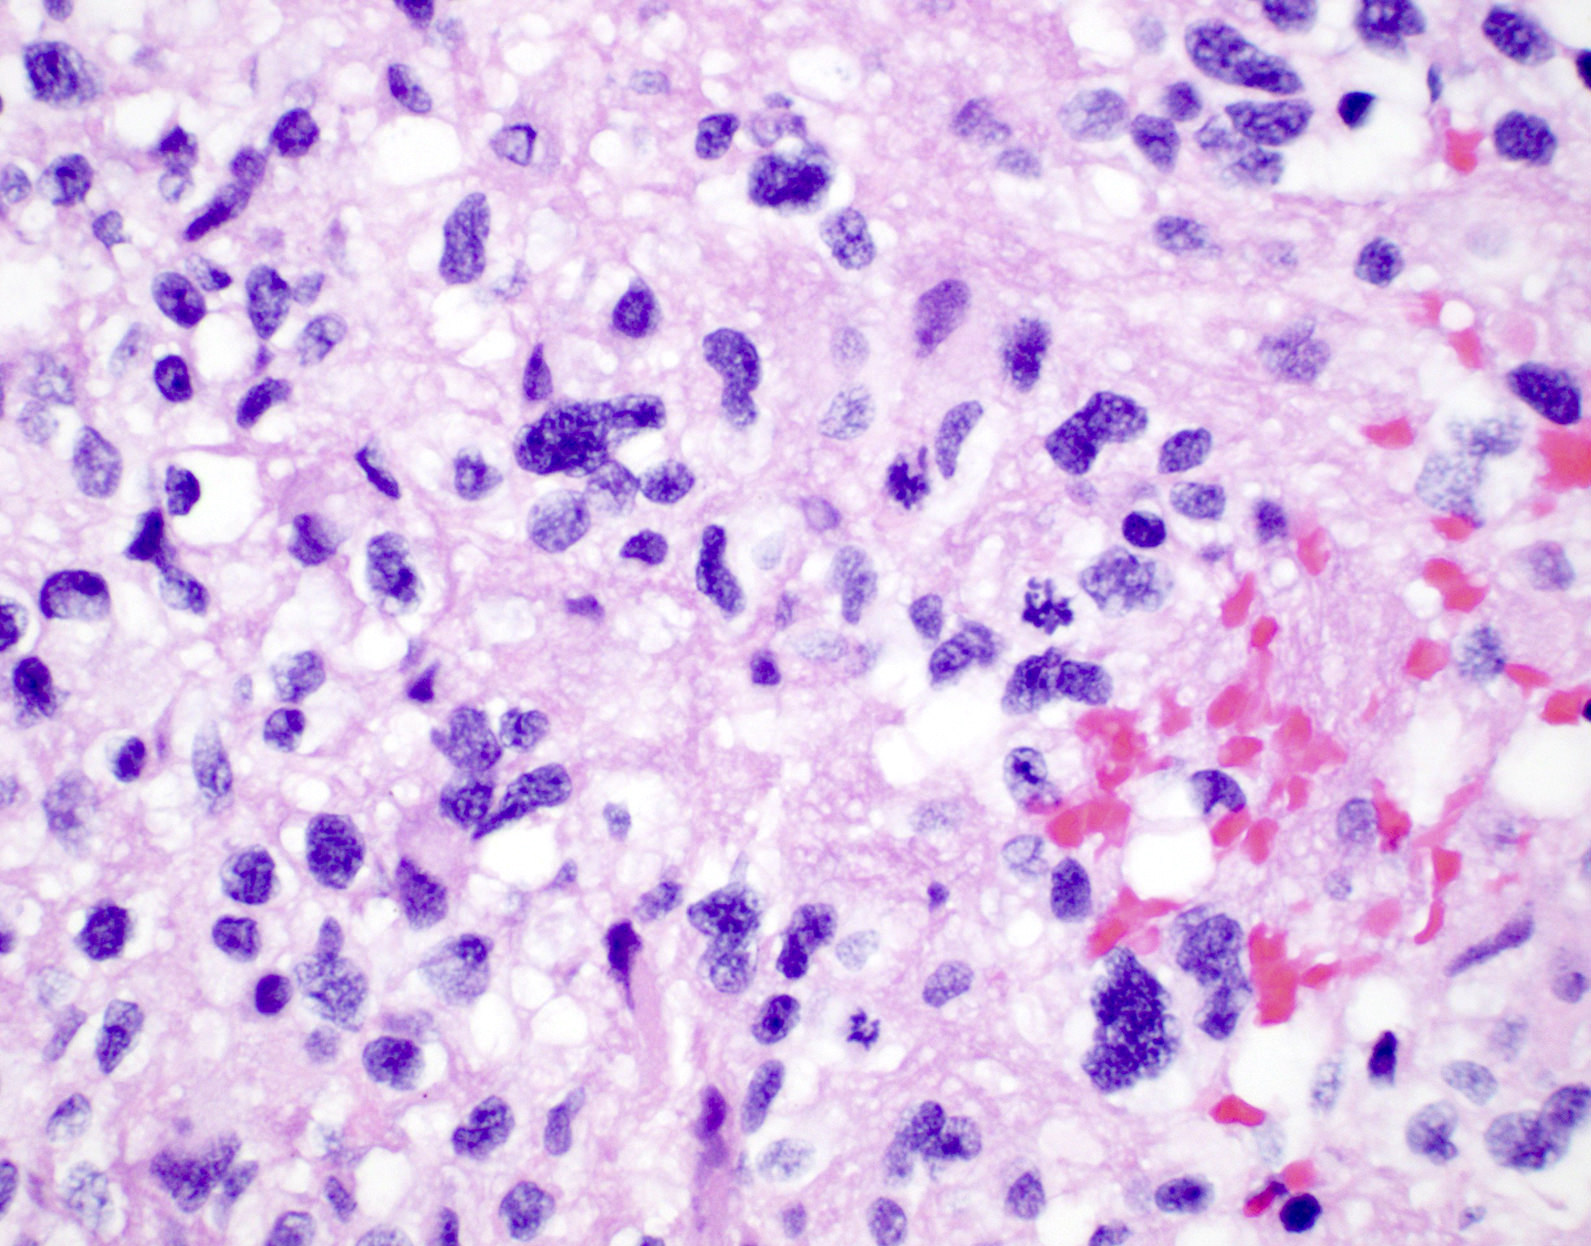

Microscopic (histologic) description

- Diffusely infiltrating tumor cells with oval to elongated astrocytic nuclei and varying appearance of tumor cytoplasm and fibrillar glial processes (Acta Neuropathol 2015;129:789)

- At the periphery, tumor cells may infiltrate in a diffuse single cell pattern, often with entrapped neurons and axons

- Cellular morphology is variable, even within a single tumor

- Commonly there is a mix of cells with elongated nuclei and fine fibrillar processes, cells with eccentric nuclei and glassy eosinophilic cytoplasm (gemistocytes), larger pleomorphic cells and small cells with scant cytoplasm

- May show oligodendroglioma-like areas

- Myxoid background and microcyst formation may be present

- Variable mitotic activity, cellularity and nuclear atypia depending on CNS WHO grade

- In small biopsy specimens, the presence of 1 mitosis may be sufficient for a CNS WHO grade 3 diagnosis, while the presence of a few mitotic figures in a large resection would not be sufficient for grade 3 designation (Acta Neuropathol 2020;139:603)

- Presence of necrosis or microvascular proliferation would be consistent with a CNS WHO grade 4 designation

Microscopic (histologic) images

Contributed by Eman Abdelzaher, M.D., Ph.D., John DeWitt, M.D., Ph.D. and Meaghan Morris, M.D., Ph.D.

B. If R132H IDH1 immunohistochemistry is positive, ATRX staining of tumor cells is expected to be lost. The image is consistent with an infiltrating astrocytoma with significant pleomorphism and mitotic activity. If R132H IDH1 immunohistochemistry is positive, as stated in answer B, the findings are then consistent with astrocytoma, IDH mutant, CNS WHO grade 3. Astrocytoma, IDH mutant tumors often show concurrent ATRX mutation, indicated by loss of staining in tumor cells with ATRX immunohistochemistry.